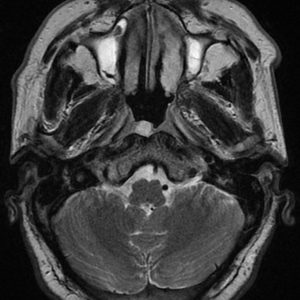

U dây VIII

Lượt xem: 140» 24-11-2018 -

U dây VIII

Lượt xem: 131» 24-11-2018 -

U dây VIII

Lượt xem: 143» 24-11-2018 -

U dây VIII

Lượt xem: 155» 24-11-2018 -